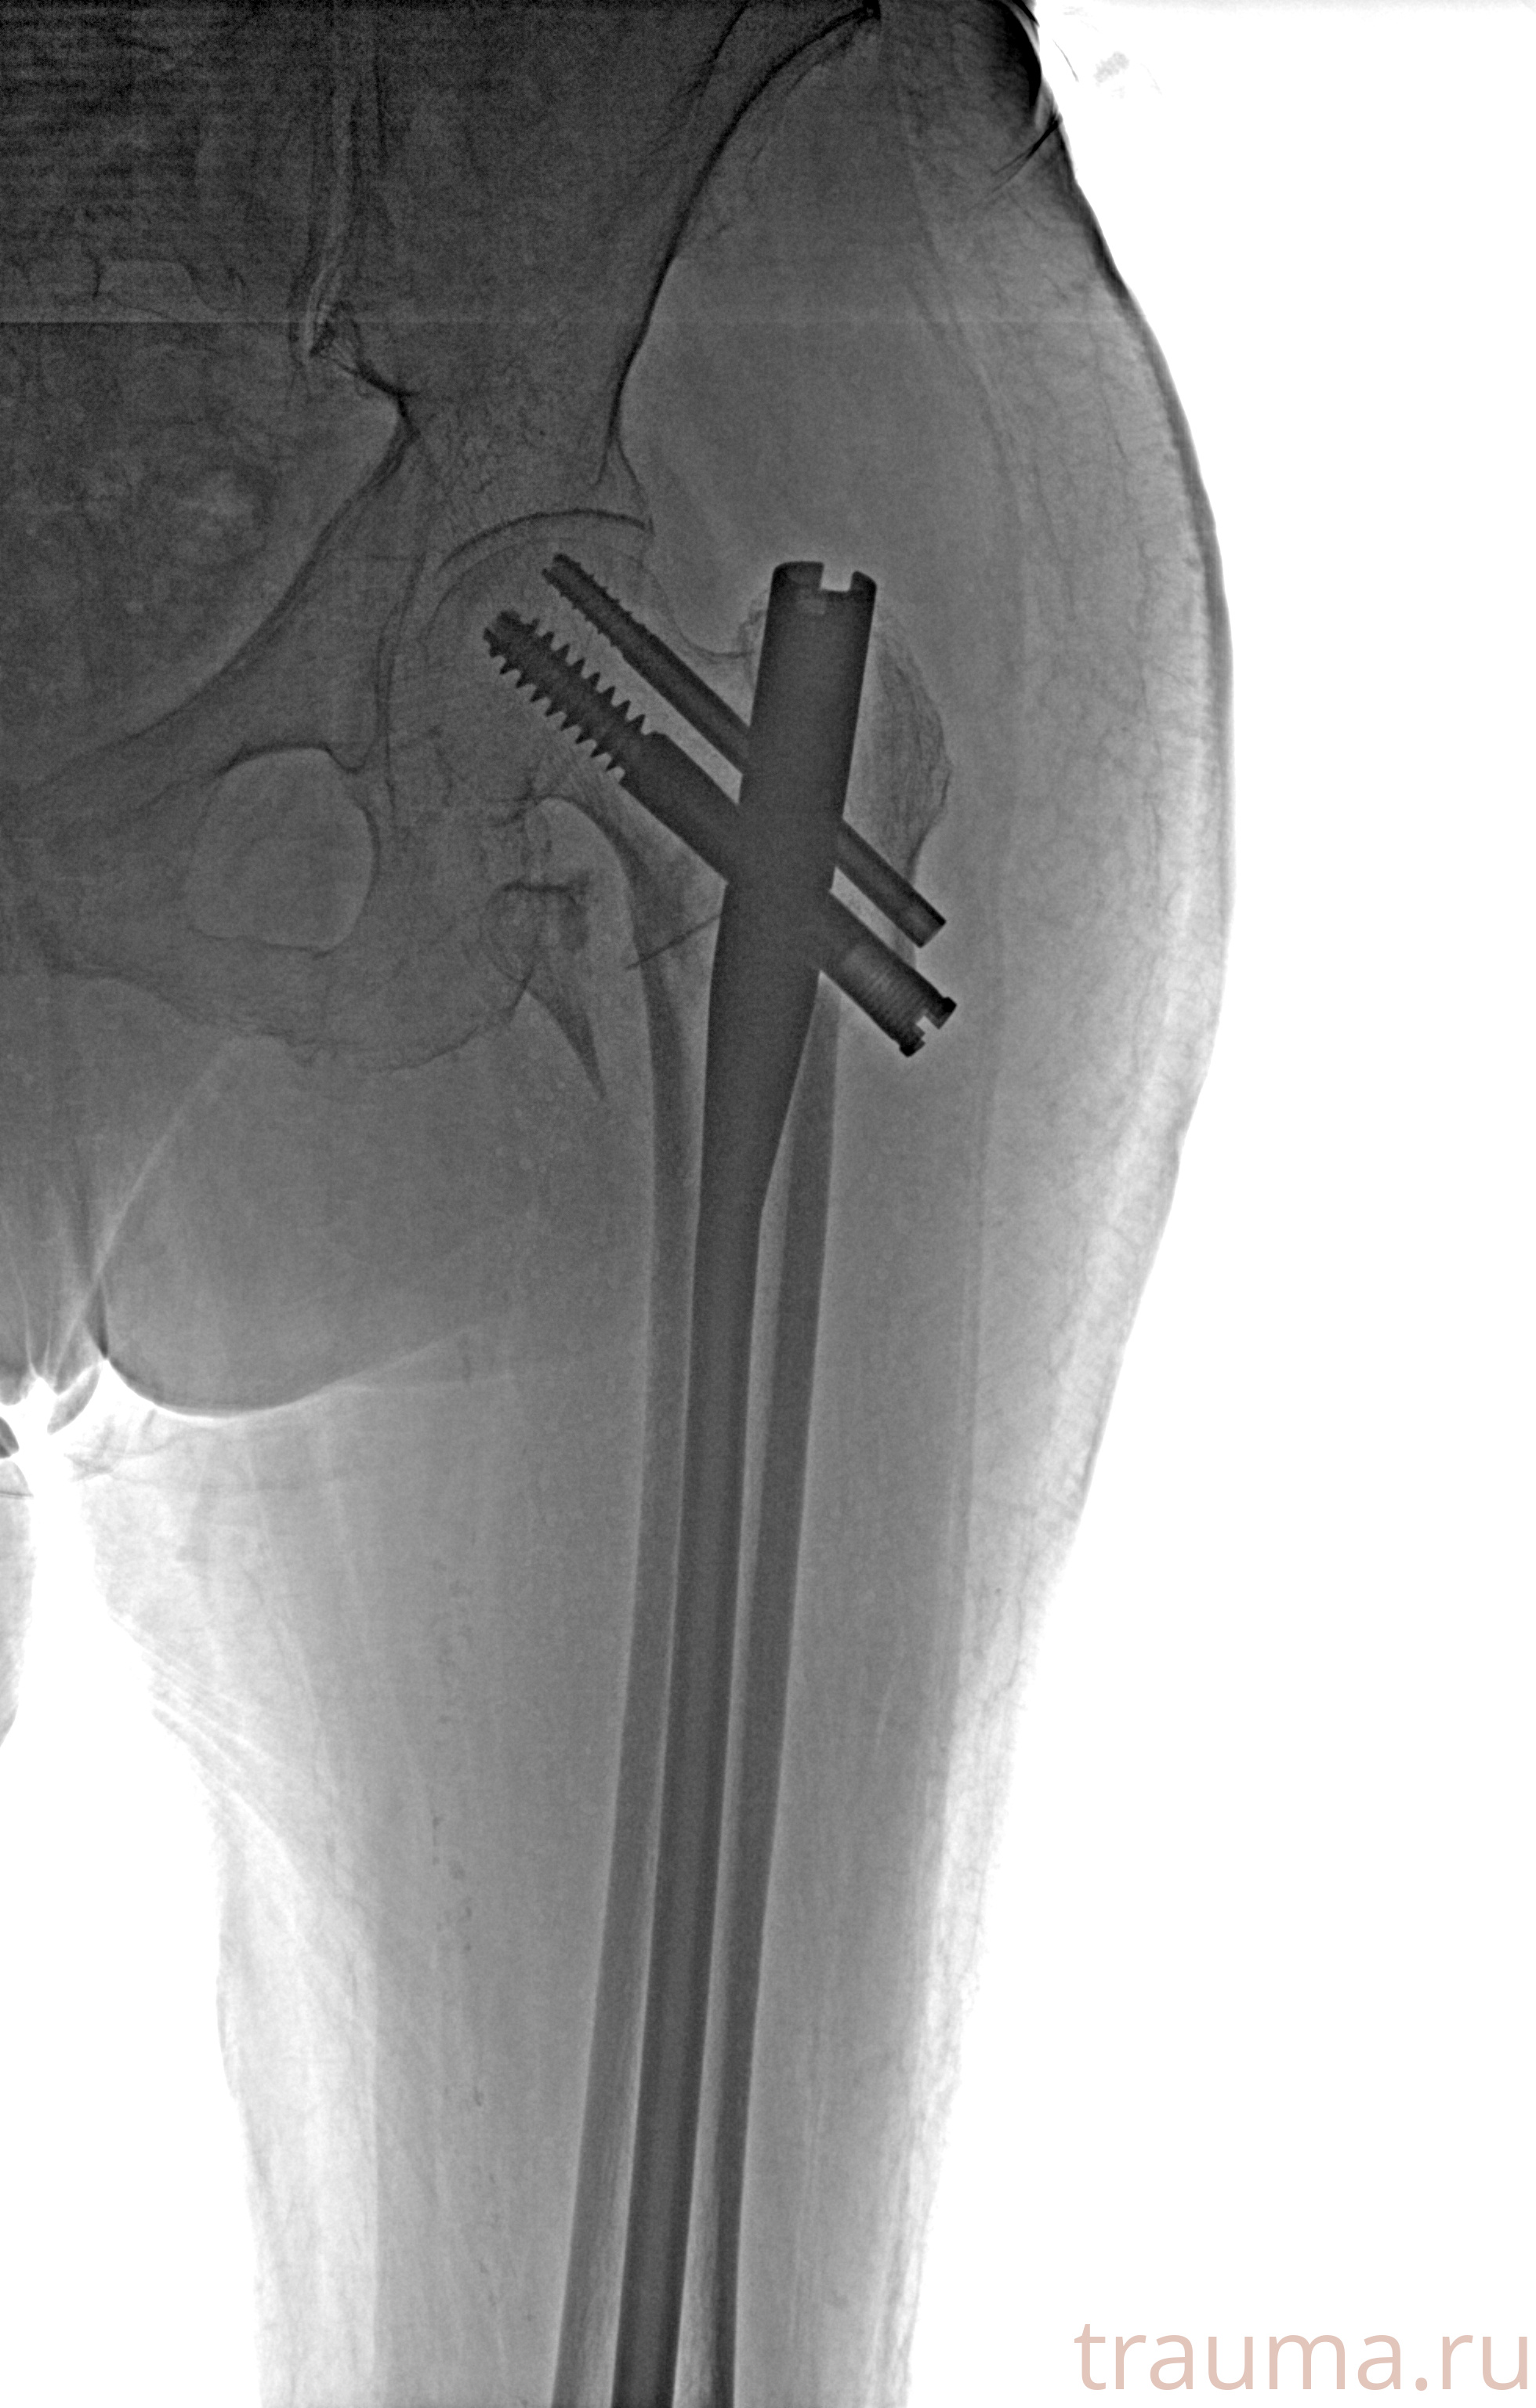

Рентгенограммы

Рентген на дому: по вашему адресу приезжает врач-рентгенолог, травматолог-ортопед с мобильным рентгеновским аппаратом, проводит диагностику травмы или заболевания, делает необходимые рентгенограммы, дает рекомендации по дальнейшему лечению. Получить качественные снимки в домашних условиях возможно благодаря уникальной методике, разработанной МосРентген Центром для института  Склифосовского